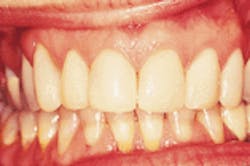

I recently received a case that had been prepared for six upper anterior porcelain veneers. The patient had had three sets of veneers placed, the last of which cracked while being placed (Figure 1). Initially, the patient had the veneers done to whiten her teeth. She had severe tetracycline staining. After a thorough examination, Phase I dentistry-consisting of caries control in posterior teeth, periodontal therapy and occlusal therapy-was completed. Full-coverage crowns using the IPS Empress System from Ivoclar were planned on Teeth #6-11. This is a pressed ceramic system that produces a more fracture-resistant ceramic material and enables the technician to use a layering technique for a beautiful esthetic result. On a new set of mounted, postequilibration models, a diagnostic wax-up was completed using the golden proportion (Figure 2). The Golden Rules cards from Thomas Dawson, DDS, Arlington, Texas, provided guidance in achieving the best esthetic harmony. A Siltec matrix (Ivoclar) was made on the diagnostic wax-up to be used in the indirect fabrication of provisionals. The provisionals then would be used to work out esthetics and function prior to finalizing and to communicate to the lab. The lab will use the cross-mounted approved provisional model to serve as a guide in fabricating the final restorations.

Figure 1